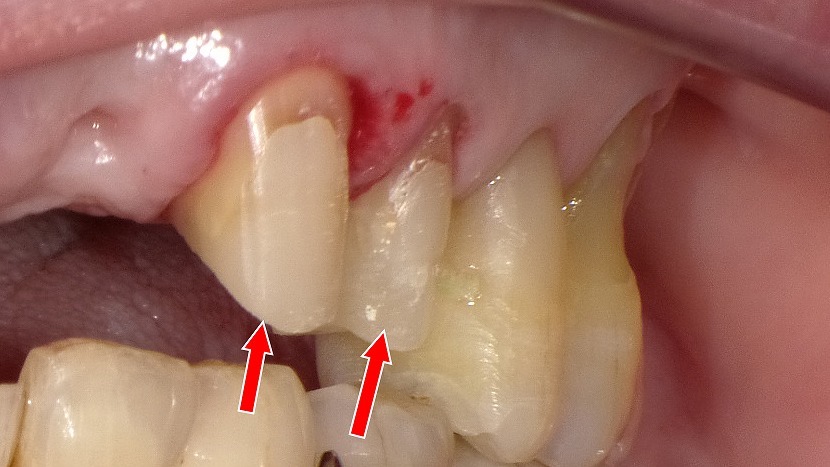

◆ コンポジットレジンの境目が茶色くなる理由|辺縁変色の典型例

赤い矢印の部分に、コンポジットレジン(CR)充填の境目の変色が確認できます。

これは、詰め物自体の変色ではなく、主に以下のような理由で境界(マージン)が着色して見える現象です。

● 辺縁が変色する主な原因

① レジンと歯の境界にできた微小な段差・隙間

年月が経つと、レジンのわずかな摩耗や接着劣化により

**歯とレジンの境目に極細の隙間(マイクロリーケージ)**が生じます。

ここにプラークや着色物が入り込み、茶色〜黒っぽく変色します。